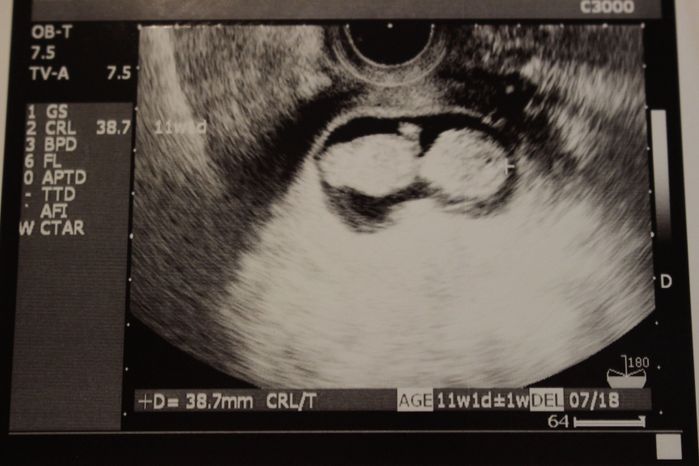

妊娠11週目のエコー写真

首や手などが見えて、すっかり人間らしくなりました。世間は年末年始の帰省ラッシュに入る頃でしたが、このときばかりは安全第一を理由に、大掃除も飛行機利用の夫の実家への帰省も取り止め、自宅でのんびり過ごしました。